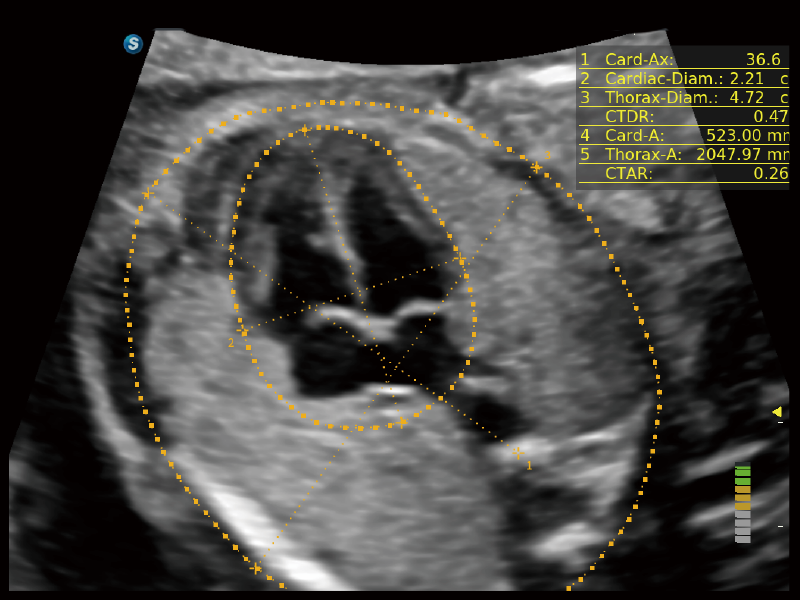

S-Fetus? 鳳眼(A4C切面)